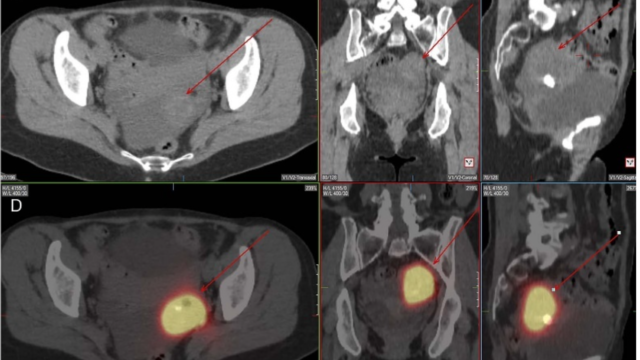

副腎皮質過形成81.3%

クッシング症候群の徴候を伴わない高血圧および/または生物学的高コルチゾール血症を伴う両側性副腎過形成(BAH)を呈する100人の患者のコホートにおけるNR3C1変異の有病率が評価された。

このグループでは、5つのNR3C1のヘテロ接合型変異が発見され、GR変異の有病率は5%となり、BAHの新たな主要な遺伝的原因となっていることがわかった。

両側副腎皮質腫大についての鑑別は以下のまとめを参照。